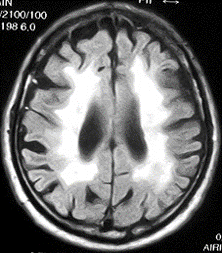

実際、外来でも依然と比較しますと脳血管性認知症の割合が極端に減ってきているのを感じます。また、認知症研究の第一人者でもある慶応大学メモリーセンター長

伊東大介教授は血圧コントロールが改善した結果、上のMRI検査のようなBinswangerタイプの脳血管性認知症を見ることがなくなったと話されています。加えて中~壮年期の脳出血患者が減っていることも体感しています。確実に血圧コントロールの厳格化が各種疾患に好影響を及ぼしている証と考えます。